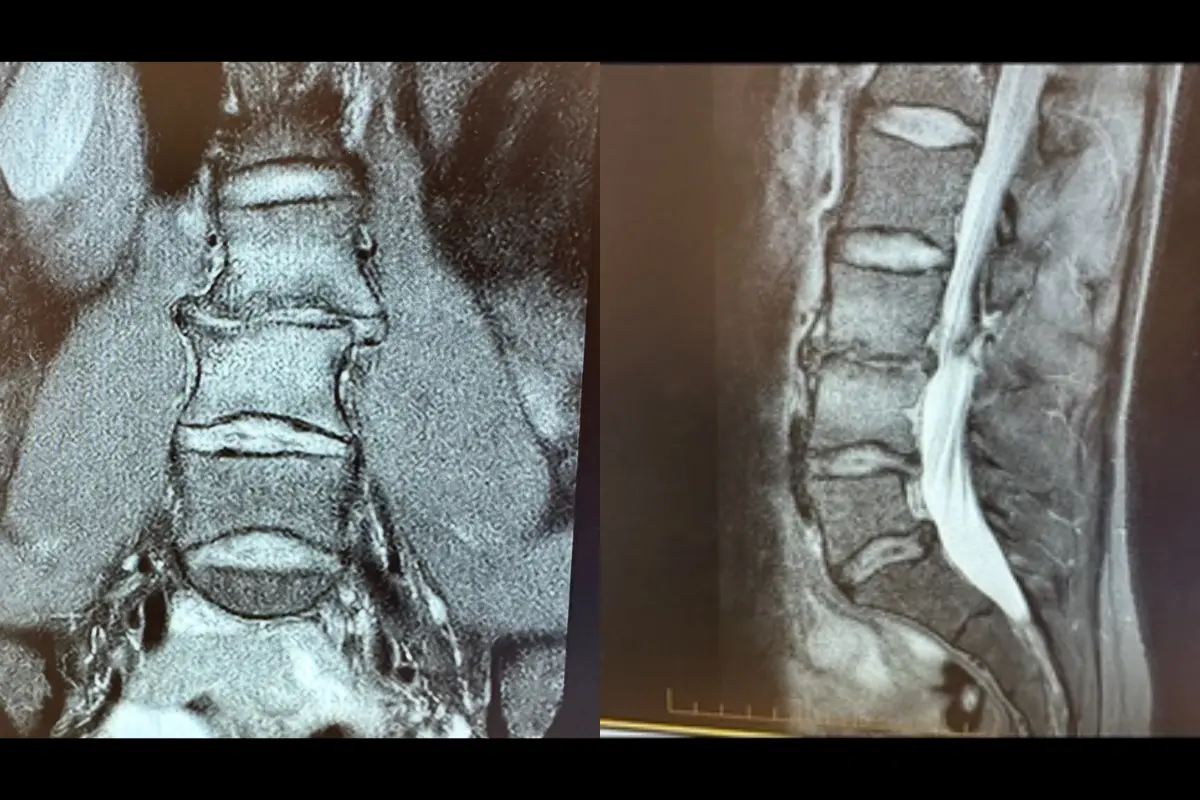

Having lost her ability to run, jump and sprint to her normal capability she decided to have surgery in March 2024 to repair the multiple fractures in her back and an almost non-existent disc, resulting in bone one bone impact in her vertebrae.

I made the decision to go ahead with the surgery and get a spinal fusion and disc replacement done,